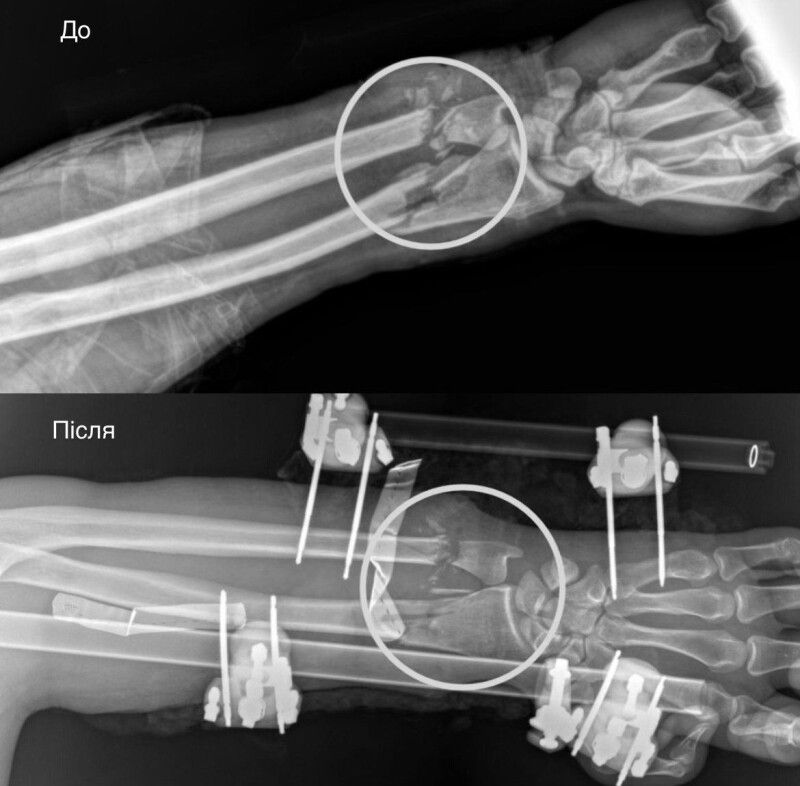

Травма була критичною: повністю пересічені артерії, пошкоджені кістки, сухожилля, м’язи та нерви. Рука фактично трималася лише на шкірі. За порятунок кінцівки взялася велика мультидисциплінарна команда, а кожна хвилина була на вагу золота.

Першими свою роботу в операційній виконали ортопеди-травматологи. Вони стабілізували переламані кістки передпліччя за допомогою апарата зовнішньої фіксації. Після чого вже судинні хірурги взялися відновлювати кровопостачання. Цей етап був вирішальним, адже без циркуляції крові тканини б швидко змертвіли. Однак, на щастя, хірургам вдалося успішно зшити судини.

Під час третього етапу хірурги зайнялися вже м’якими тканинами. Аби відновити згинально-розгинальну функції руки, ушили пошкоджені сухожилля і м’язи. А нерви підготували до подальшої операції, яка відбудеться через місяць-два. Завершилося це багатоетапне втручання аутодермопластикою, під час якої реконструктивні хірурги закрили дефект власною шкірою пацієнта.